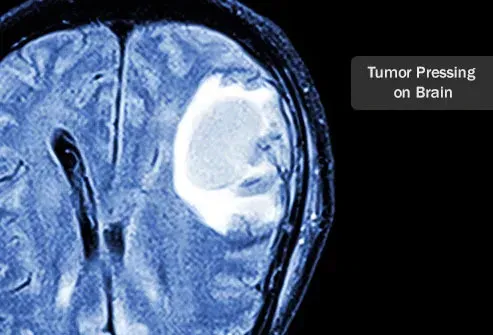

Dangers des tumeurs cérébrales

Le crâne est un cadre dur d'os. Les tumeurs dans le cerveau sont dangereuses car elles font pression sur les zones du cerveau à mesure qu'elles se développent. Le crâne n'est pas en mesure de se développer pour s'adapter à la présence d'une tumeur. Lorsque la tumeur grandit, elle se poursuit sur le cerveau. Selon la zone du cerveau affectée, cela peut entraîner des problèmes de réflexion sur la vision et le sentiment d'action. Les facteurs qui déterminent à quel point une tumeur cérébrale est dangereuse comprend l'emplacement, qu'il soit ou non enlevé chirurgicalement et à quelle vitesse il se développe et s'il a la capacité de se propager ou non.